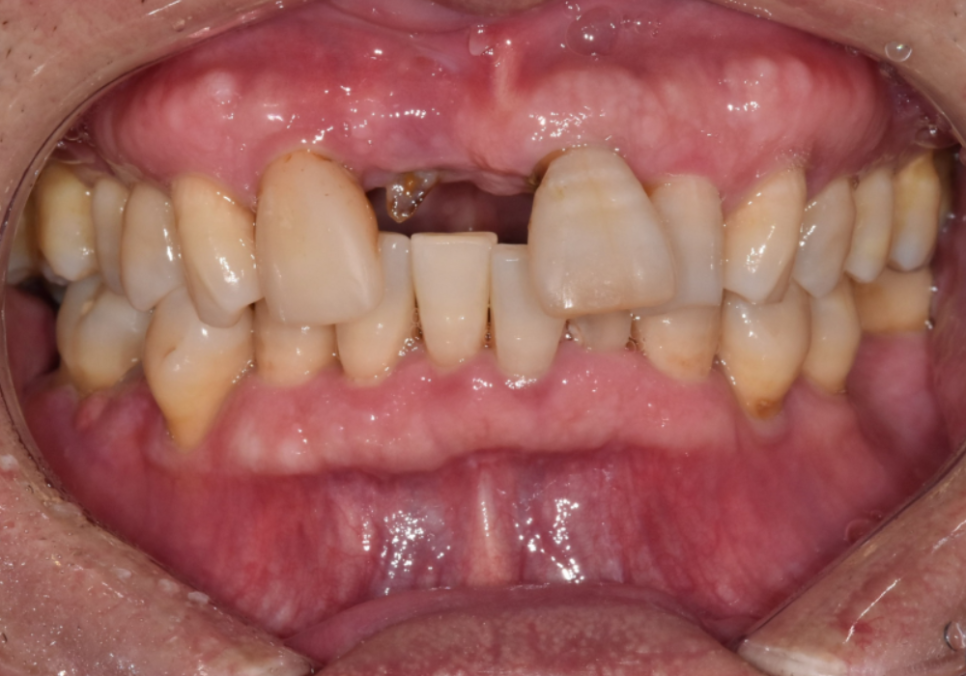

최근 앞니가 빠져

내원하신 환자분 사례입니다.

입안을 살펴보니, 오른쪽 앞니(#11)는

이미 부러져서 뿌리만 남은 상태였고,

왼쪽 앞니(#21)는 동요도 3도로

확인될 만큼 심하게 흔들리고 있었습니다.

뿐만 아니라 충치도 꽤 깊게 진행 중이였어요.

환자분의 경우 빠진 치아 옆 치아마저(#12)

약간 흔들리고 있어서,

브릿지로 하기엔 무리가 있었어요.